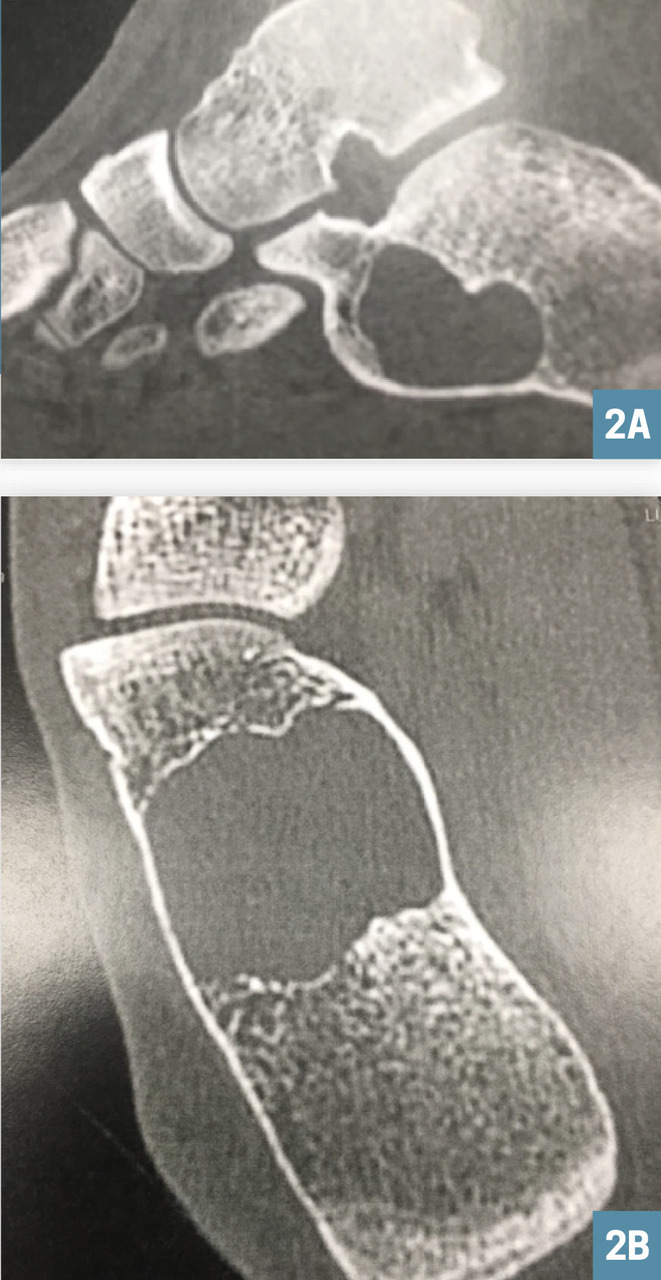

Ces examens permettent de poser le diagnostic de kyste osseux essentiel calcanéen, lésion bénigne qui ne nécessitera qu’une surveillance radiologique (fig. 2A et 2B).